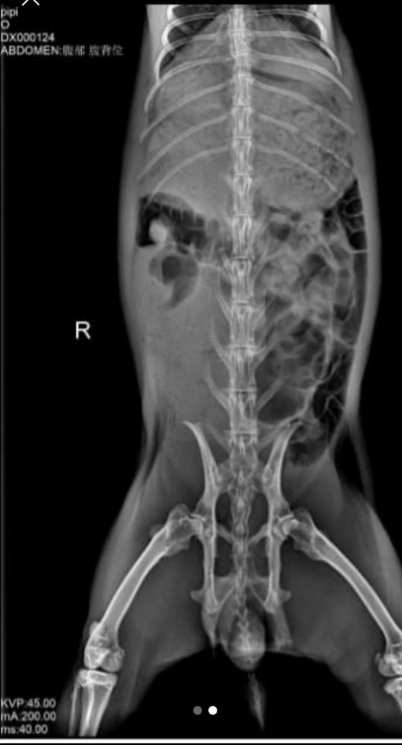

Today, we treated a 7-year-old rabbit whose owner brought it to the clinic after noticing that the rabbit was unwell. The rabbit had a poor appetite, reduced fecal output, and the feces were smaller than usual. What concerned the owner most was the rabbit